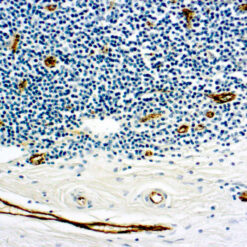

ERCC1

This antibody reacts with a 33-36 kDa protein known as ERCC1 (excision repair cross complementing) polypeptide. ERCC1 is required for nucleotide excision repair of damaged DNA and is homologous to RAD10. In mammalian cells, XPG cleaves 3’ of the DNA lesion while ERCC1-XPF complex makes the 5’ incision.

| Positive Control Tissue | Tonsil |